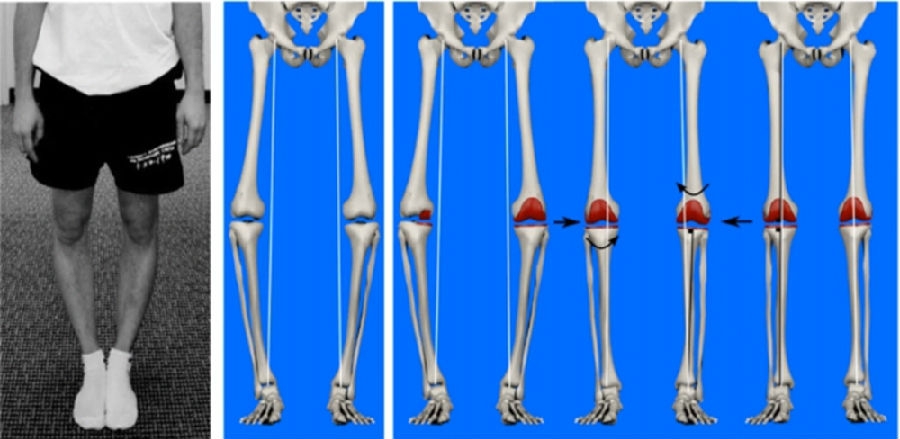

图1

①调整机械轴对线(aMA),在MA基础上衍生而来,胫骨截骨面与胫骨机械轴呈90°,通过调整股骨侧截骨量和假体位置,保留冠状面上轻度关节畸形(<3°);

②运动学对线(KA),基于患者个性化的股骨屈曲轴、胫骨平台旋转轴和髌骨屈曲轴三轴定位,实现完全解剖位置的TKA假体植入,恢复患者自然的下肢力线;

③限制性运动学对线(rKA),遵循KA的主要技术原则,保留股骨侧假体的运动轴对线,通过微调胫骨侧假体的位置来调整下肢力线和关节面倾斜度;

④解剖轴对线(AA),特点是保留关节面2°~3°倾斜,恢复生理关节线;

⑤功能学轴线(FA),机器人辅助精准截骨和安放假体位置恢复关节线高度、膝关节生理内翻倾斜度和内外侧屈伸间隙平衡,恢复下肢力线于0°±3°安全范围内。

研究表明这些TKA对线技术的应用能够取得良好的临床疗效,但是应用于严重畸形病例仍具有一定的局限性。原因在于aMA、rKA、AA和FA这四类对线技术的目标下肢力线范围在0°±3°内,仅通过截骨矫正畸形程度有限,仍需适当松解软组织以恢复屈伸间隙的平衡。此外,KA对线技术仅通过截骨进行解剖重建,术后残留畸形度数往往超出0°±3°范围,而目前下肢力线的安全范围尚无绝对统一标准。